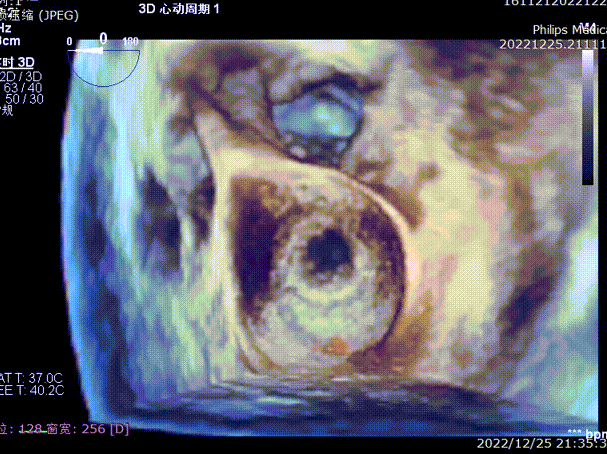

3D条件下测量衰败生物瓣瓣环内径